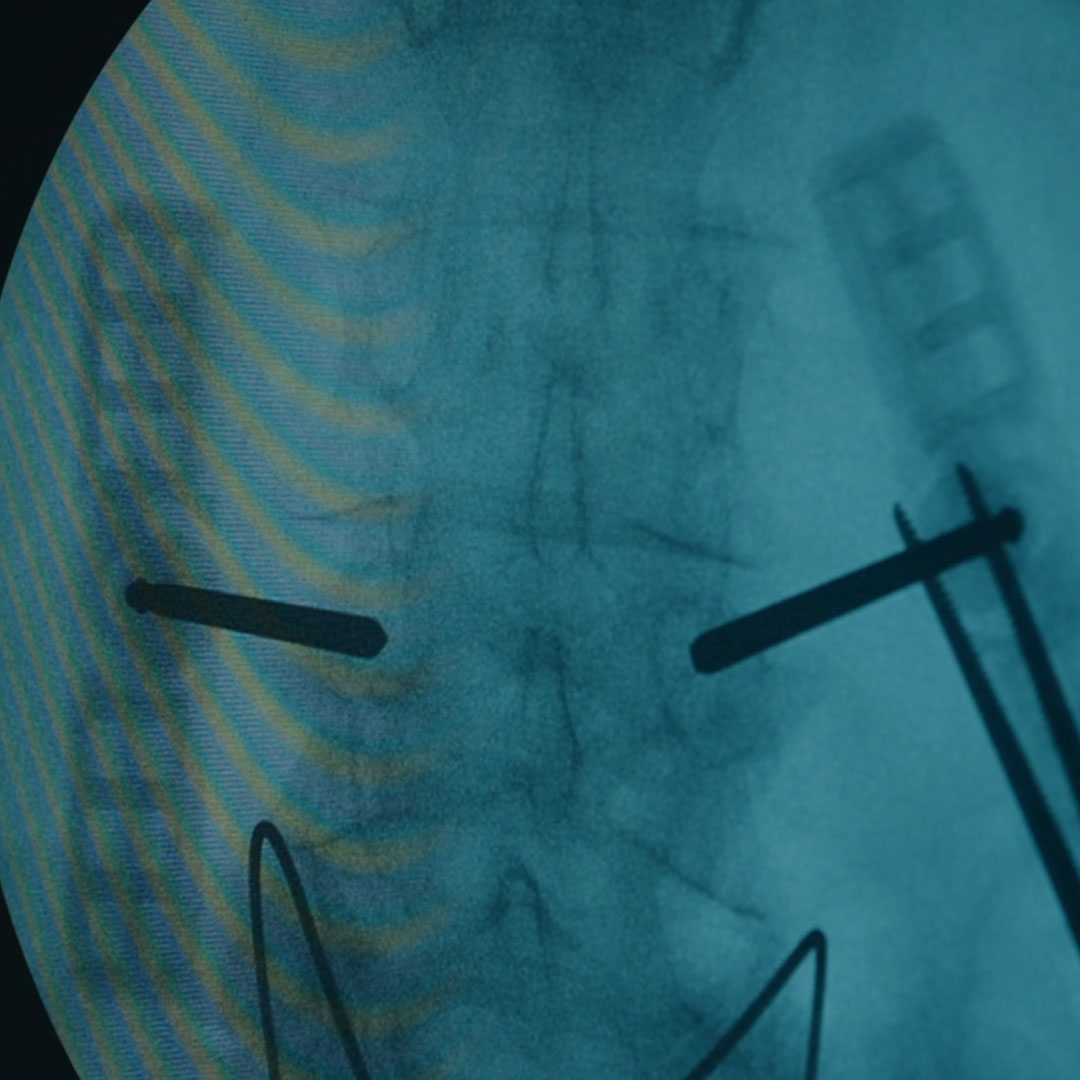

Performed by Neurosurgeon Dr Leandro Ribeiro from the HPA Saúde Group, kyphoplasty is a minimally invasive, rapid, and safe procedure with excellent clinical outcomes. The treatment involves making small incisions through which a cannula is inserted. Using specialised devices, it is then possible to restore the height of the affected vertebra.

Subsequently, the fracture is stabilised with bone cement, providing strength and solidity to the fractured vertebra.